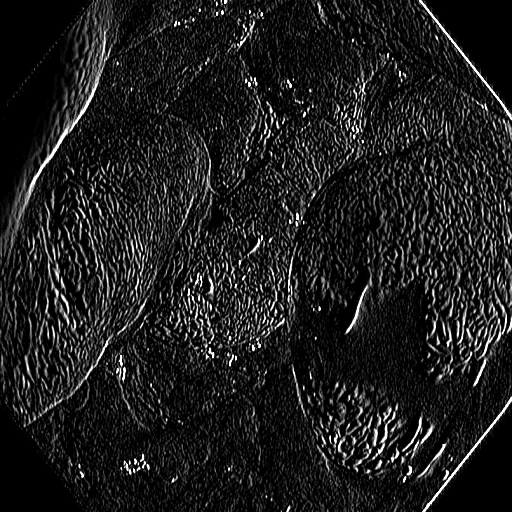

The Edge-Guided Feature Enrichment (EGFE) unit actively enhances feature representation by integrating edge knowledge into the set of features. It applies a Sobel operator to the input feature set, generating separate gradient magnitude maps for horizontal and vertical directions (Fig. 3). As illustrated in Fig. 3, the Sobel operation in a single direction captures limited information about the polyp. However, combining these maps (Fig. 3(d) and Fig. 3(h)) effectively captures polyp boundaries and enriches learned features. The final gradient magnitude map, produced using the Euclidean norm (Eq. 1), highlights regions with significant intensity changes at polyp boundaries.

Fig. 7 offers qualitative validation, showcasing MNet-SAt’s superior polyp mask generation compared to baselines across four cases. This qualitative superiority aligns with the previously established quantitative results. In the case of small polyps (first and fifth rows), all baseline methods initially appear to produce satisfactory visual results. However, upon closer inspection, they fail to maintain fine boundary details. Our framework excels in preserving polyp anatomy and topology for medium and large polyps, significantly outperforming the baseline methods. Notably, even in multiple polyps, our framework successfully captures more polyps and approximates the ground truth more closely. The primary reason for this superior performance is the EGFE module, which effectively eliminates noise in conjunction with the HMAtt module, resulting in a few false positives. Our analysis reinforces MNet-SAt’s effectiveness in handling challenging polyp scenarios (small, medium, large-scale, and multi-polyps) while suppressing non-regions of interest.